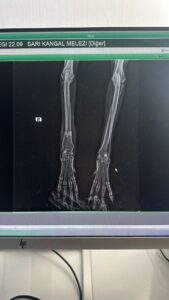

This dog, who came to the shelter with a broken leg, had surgery at Cadde Clinic. He’s doing well. He’s starting to walk again. Unfortunately, we don’t have a place to put him, so he’ll be returning to the shelter. He’ll be housed in a special place at the shelter until he can walk normally again. He’s a large dog suitable for shepherding sheep and cow farms. Male. 30 kg. 5-6 years old. Available for adoption from the shelter. We desperately need your support to care for this dog and many more. Please help us within your budget, so we can help them too.